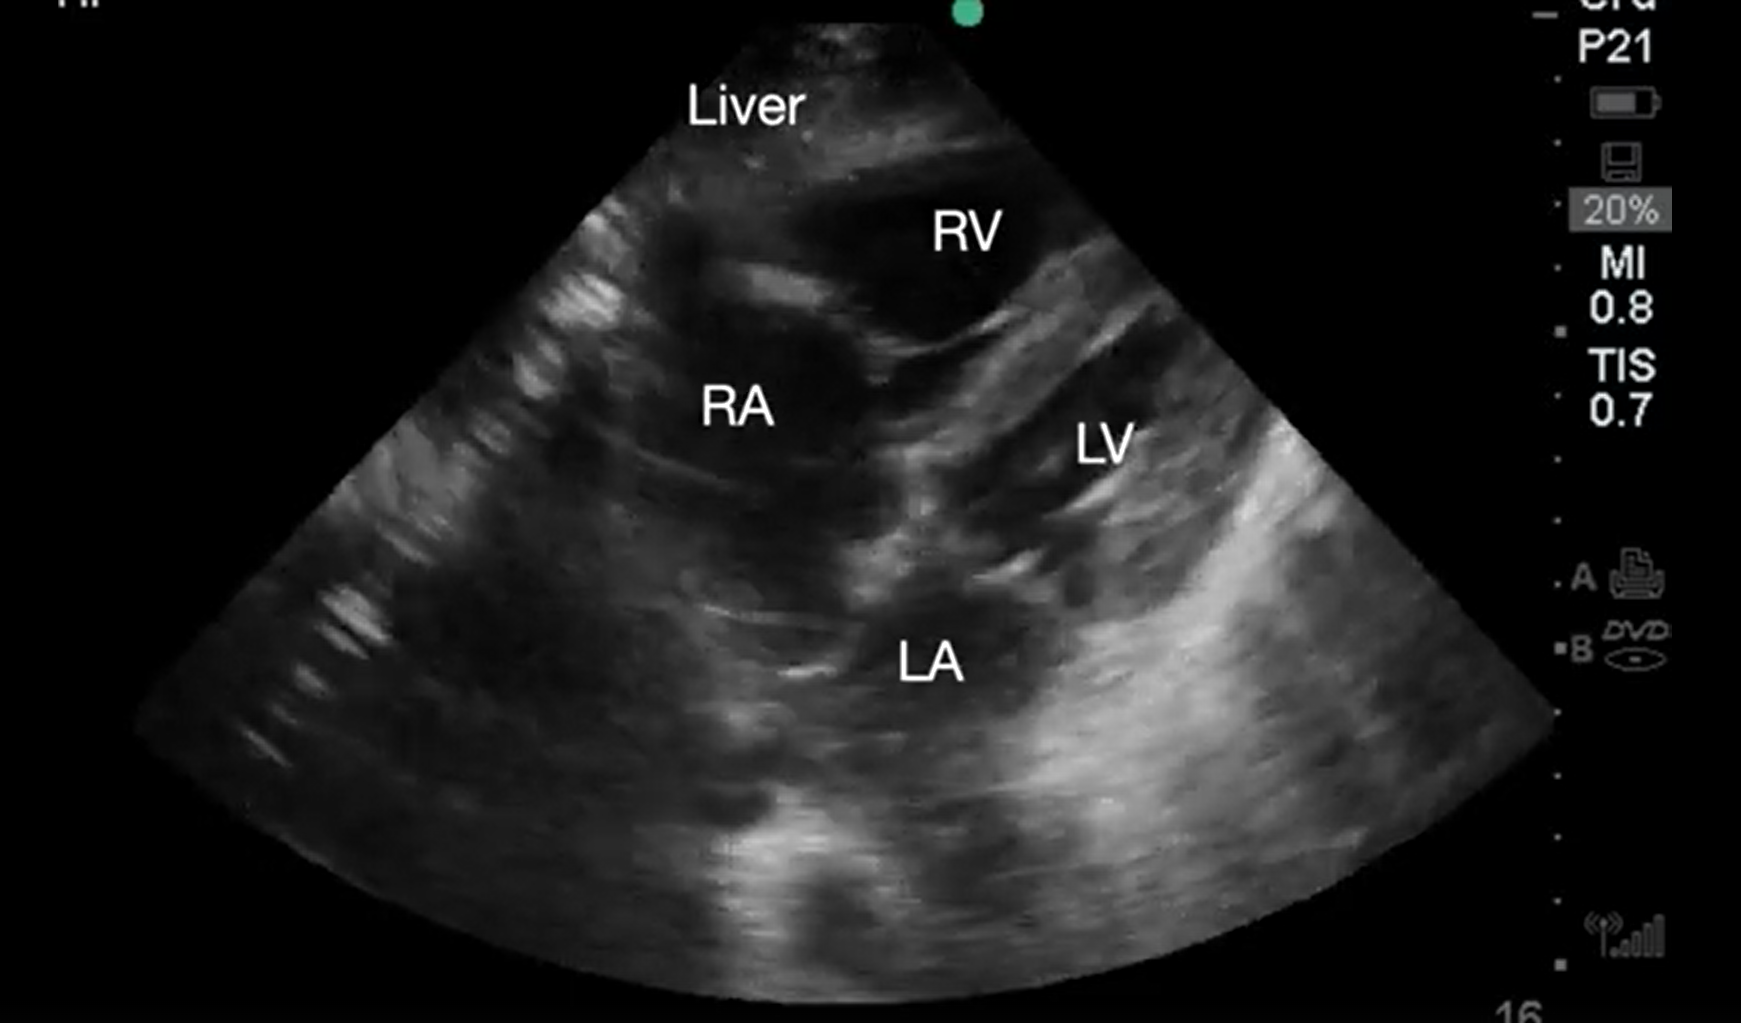

Video 1. Subcostal 4-chamber view demonstrating cardiac standstill. RA, right atrium; LA, left atrium; RV, right ventricle; LV, left ventricle (click to view)

Video 2. Subcostal 4-chaber view demonstrating pericardial effusion. RA, right atrium; LA, left atrium; RV, right ventricle; LV, left ventricle (click to view)

The responding resident is alerted to an acutely decompensating patient in the SICU or medical or surgical ward by direct call from the primary service or by overhead Code Blue page. On arrival, the resident prepares to serve as a sonographer and complete an EASy-ALS exam. The ultrasound probe is placed in the subcostal window before the pulse/rhythm check without obstructing chest compressions. The code leader, a senior primary care team provider, is responsible for holding and resuming chest compressions. The code leader assigns a nurse to count down 10 seconds during the pulse/rhythm check; this is standard at our institution. After resumption of chest compressions, the resident interprets recorded images and communicates findings to the code leader. The primary phenotypes (Figure 2) to be identified are cardiac standstill (see Video 1), pericardial effusion (Video 2), dilated right ventricle (RV) (Video 5), dilated left ventricle (LV) (Video 6), and underfilled heart (Video 7). The resident can obtain extracardiac views (such as the subcostal IVC View, Video 3), between pulse/rhythm checks.